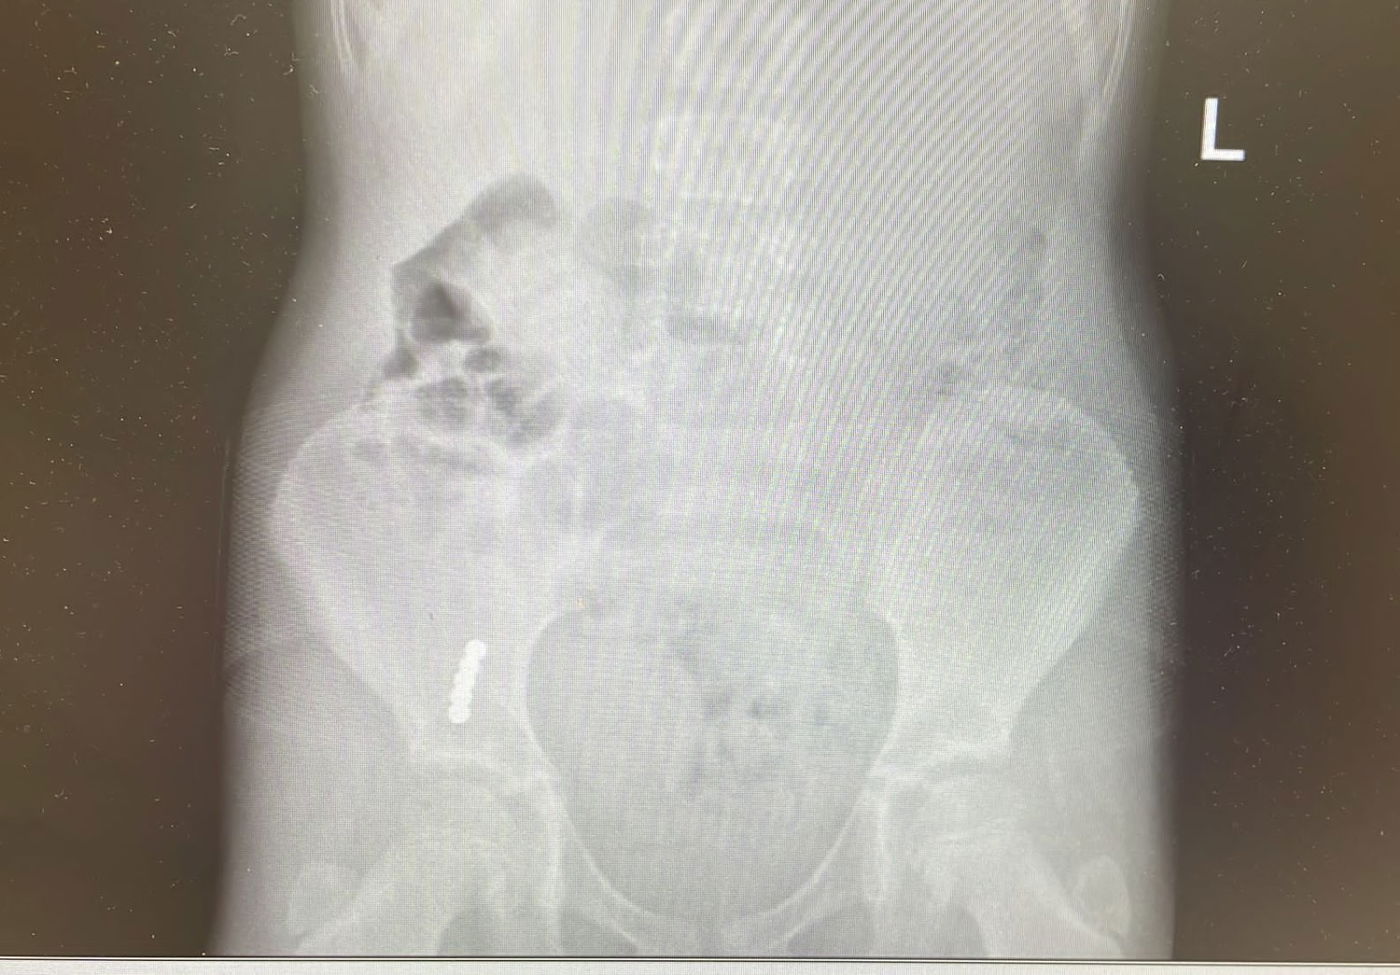

באחד המקרים בילדה בת 7, התברר בצילום רנטגן כי בלעה חלקי משחק שנתקעו במעי, ובהוראת הרופאים הובהלה לניתוח. הניתוח התבצע הבוקר ועבר בהצלחה לשמחת ההורים והצוות הרפואי.